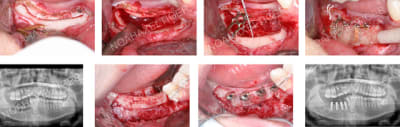

Comme je te l'avais posté, j'ai une autre approche pour les expansions verticales.

J'ai du mal à faire confiance au simple matériaux de comblement comme mainteneur d'espace ou de cale.

Soit j'utilise un bloc osseux, mais si je ne veux pas faire de prélèvement de bloc, j'utilise des plaques d'ostéosynthèse. Super simple et sûr. Tu positionnes ton bloc à la hauteur que tu désires et avec l'angulation latérale que tu souhaites.

Le hiatus est comblé avec un biomatériaux (pour moi BioOss + os autogène) et le tout recouvert d'une double membrane de Ossix.

Photos cliniques :